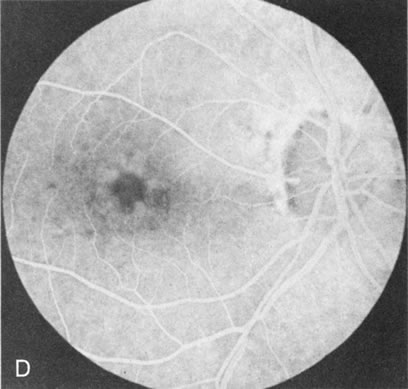

In Stargardt's disease, thes most common hereditary macular dystrophy, FA has a variety of functions. In the mildest fundus presentation, with visual symptoms and visual function out of proportion to the observed maculopathy, FA can confirm or even make the diagnosis and can avoid a mistaken diagnosis of malingering, hysteria, or central nervous system disease (Fig. 9A and B). When a maculopathy is present without surrounding parafoval flecks, FA may show patchy areas of transmission hyperfluorescence in the posterior pole, indicating a more diffuse involvement (Fig. 9C and D).

Fig. 9. Stargardt's disease–fundus flavimaculatus. The mild maculopathy (without parafoveal flecks) (A) is confirmed by the angiogram (B). The relative absence of the underlying choroidal flush, resulting in an easier visualization of the overlying retinal capillary circulation, has been referred to as the “silent” or “dark” choroid, and is considered a common finding in this disease. The diagnosis is confirmed in an individual with a pigmentary maculopathy without flecks (C). Here the angiogram demonstrates widespread transmission hyperfluorescence and a “silent” or “dark” peripapillary area (D). When the posterior pole shows multiple yellowish-white flecks (E), the angiographic findings do not necessarily correspond to the flecks (F). It should also be noted that despite the widespread abnormalities, the background choroidal fluorescence is normal.

In a large majority of patients (86% in one study),20 there is an absence or decrease in the background choroidal fluorescence (which is referred to as the “silent” or “dark” choroid) (see Fig. 9B). This warrants special attention because it occurs so frequently, is rarely found in other retinal disorders,21 and may be related to histopathology that shows an increase in lipofuscin in the RPE.22